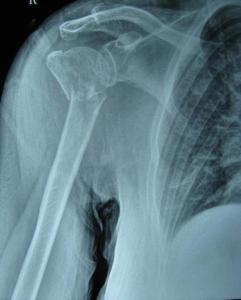

♥肱骨头骨折

单纯的肱骨头骨折比较少见,是一种关节内骨折,主要因间接外力所致。骨折多见于青壮年,偶见于老年。根据骨折的不同程度可分为肱骨头裂折、肱骨头骨折脱位及肱骨头粉碎性骨折三个类型。